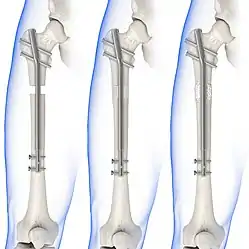

| Radiograph showing a Maisonneuve fracture of the proximal fibula | |